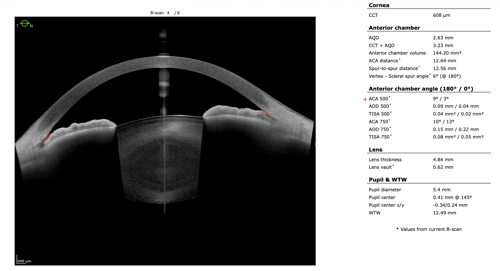

To refine surgical candidacy, anterior segment imaging was performed using the Heidelberg ANTERION SS-OCT. High-resolution imaging clearly demonstrated the following:

- A visually clear crystalline lens, not meeting criteria for cataract extraction

- Markedly narrow angles at iris insertion

- Angle measurements in the single-digit degrees